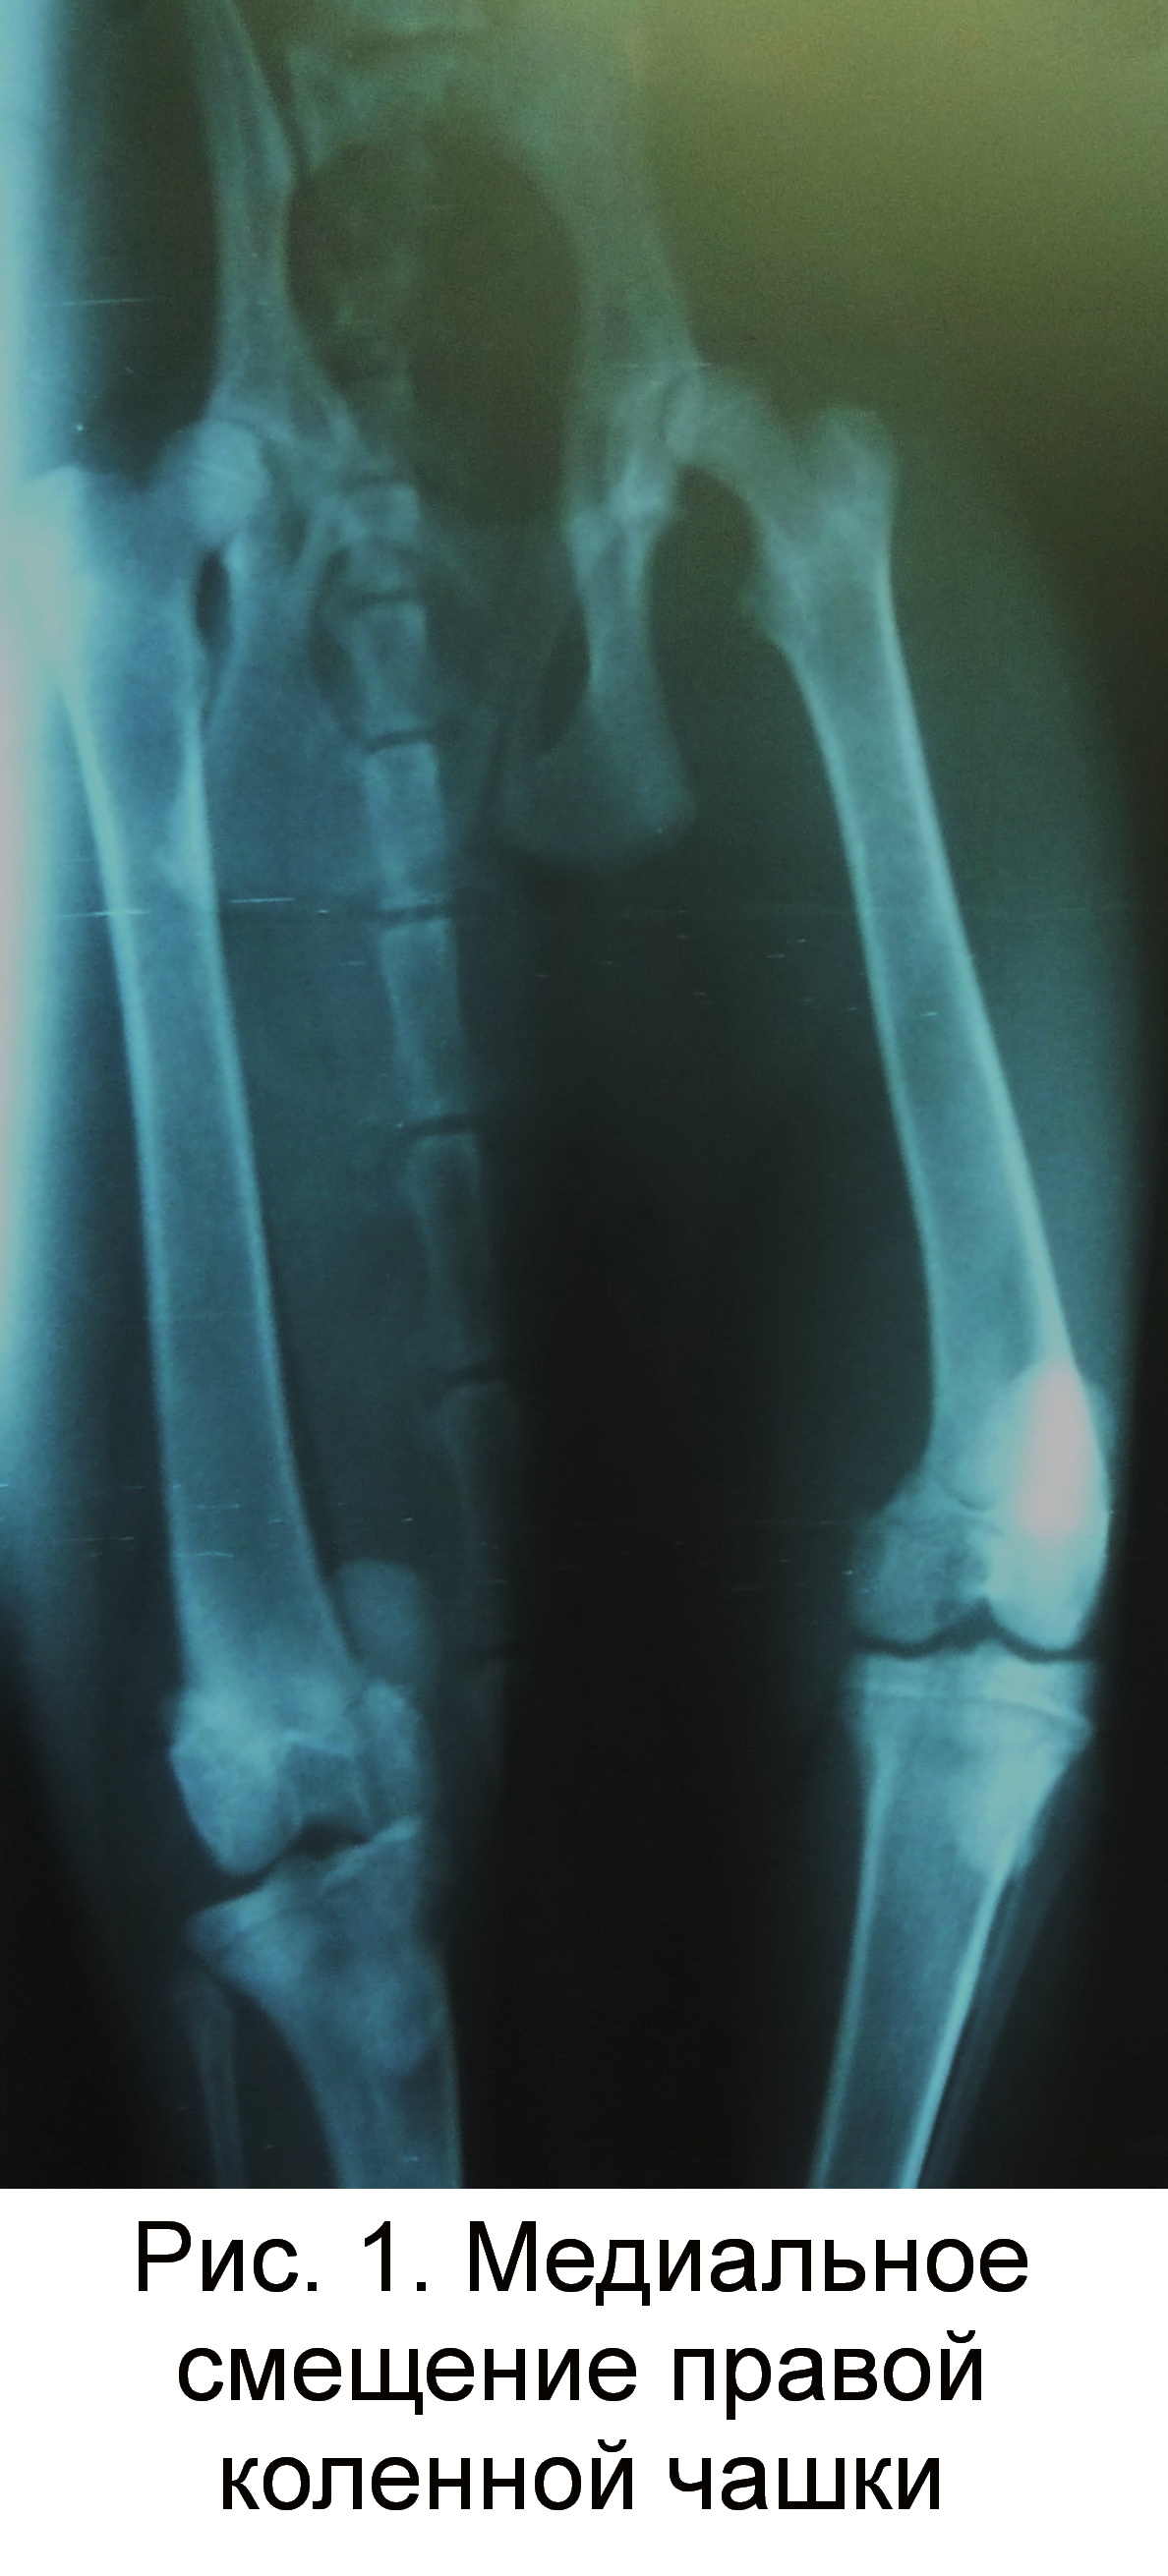

Особый вариант перелома – вертикальный, при котором линия перелома проходит сверху вниз. В подавляющем большинстве случаев такие переломы не смещаются, так как тяга мышцы направлена снизу вверх, то есть вдоль линии перелома. Однако мировой медицине известны и редкие случаи смещения таких переломов, которые могут возникнуть в том случае, когда например, мыщелки бедренной кости диспластичны и надколенник изначально был смещен в сторону (обычно кнаружи).

Сам по себе вывих надколенника возникает редко, но при врожденных аномалиях коленного сустава или как последствие других травматических повреждений колена вывихи надколенника занимают второе по частоте место среди повреждений коленного сустава. Что значит приставка «привычный»? Она говорит о периодическом повторении такой травмы.

Чтобы произошло смещение надколенника, который мы чаще называем коленной чашечкой, необходима колоссальная нагрузка на ногу. Поэтому чаще всего причиной этой травмы становятся чрезмерно активные занятия спортом и связанные с ними падения на колени, боковые удары в колено (медиальный и латеральный подвывих надколенника), резкие разгибания коленного сустава

Когда такая травма возникает, говорят об остром состоянии. Если через время надколенник снова смещается – это привычный вывих коленного сустава. Нередко он возникает после вправления острого смещения надколенника.

Если через время надколенник снова смещается – это привычный вывих коленного сустава. Нередко он возникает после вправления острого смещения надколенника.

Существует классификация по направленности костного смещения надколенника.

- Боковой — как правило появляется из-за прямой травмы колена при разогнутой голени.